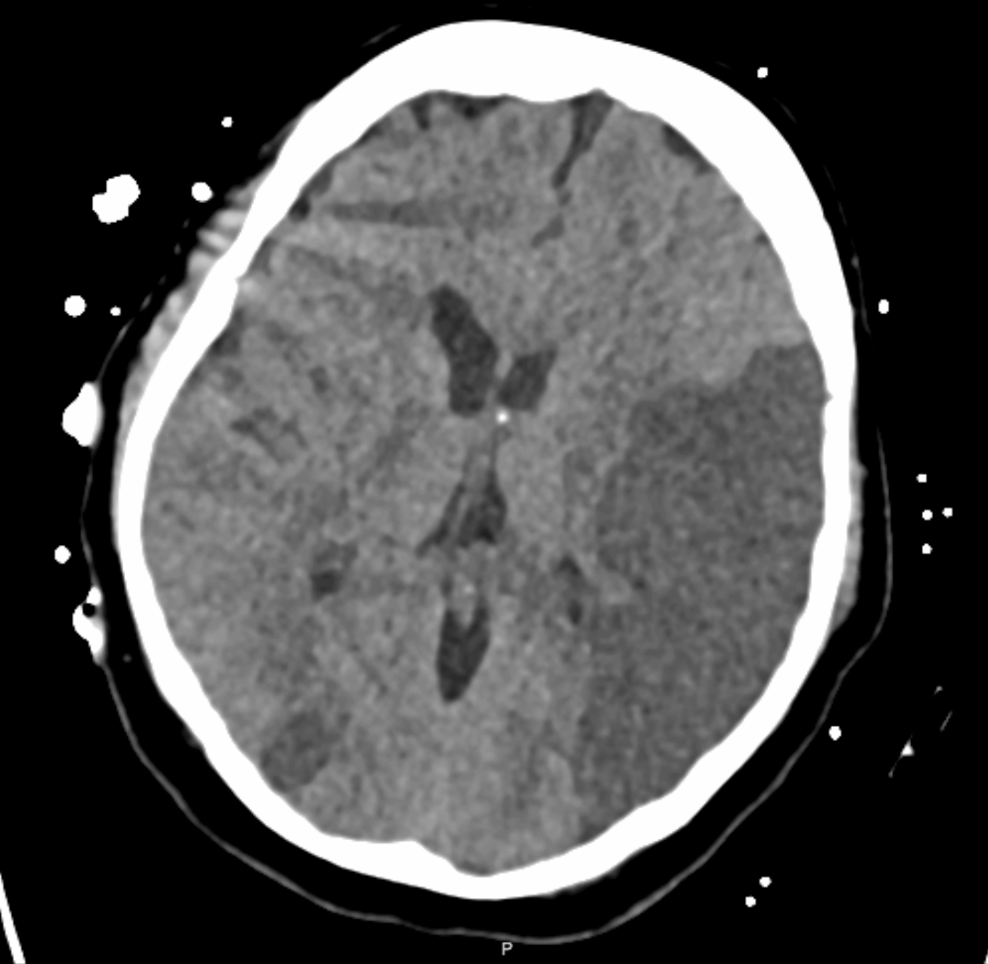

Transcranial ultrasound neuromodulation

Noninvasively modulating brain circuits with high spatial precision to enhance the way medications influence the brain (study ongoing, ask me for details).